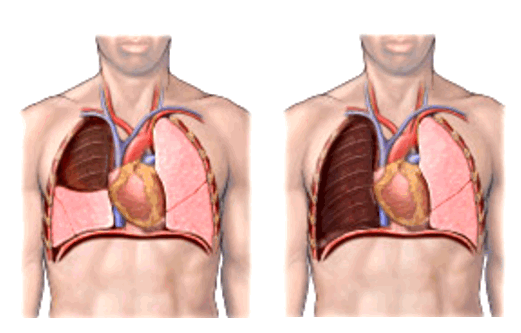

Пневмонэктомия — удаление всего легкого целиком.

Лобэктомия — удаление доли легкого, то есть анатомическая резекция доли. При удалении отдельной доли перевязываются входящие в нее сосуды и бронхи. В норме в правом легком три доли, а в левом — две. Соответственно, если удаляют одну долю справа — это одна треть легкого, удаление двух долей (билобэктомия) в правом легком — две трети, а удаление одной доли слева — половина легкого.

![Лобэктомия и пневмонэктомия]()

Фото 3 — Лобэктомия

Фото 4 — Пневмонэктомия